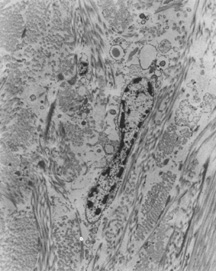

Ultrastructural studies show that developmental events of the sclera begin in the region anterior to the equator at approximately day 43.4,5 The late mesenchymal cells or very early fibroblasts of the anterior portion possess elongated nuclei and many glycogen granules and lipid vacuoles whereas those of the posterior portion possess round-to-oval nuclei and few glycogen granules and lipid vacuoles. The late mesenchymal cells or very early fibroblasts of the anterior and posterior portions contain many free ribosomes and polyribosomes, as well as immature rough-surfaced endoplasmic reticulum and Golgi complex. The early fibroblasts begin the synthesis of glycoproteins, glycosaminoglycans (especially hyaluronic acid), collagen, and elastin between day 43 and 50, thus filling the intercellular space. Developmental events directed from inside outward begin at week 7.2 with a marked increase in the inner portion in glycogen granules and lipid droplets of the cells, and in number and average diameter of collagen fibrils. Cytodevelopment of the sclera is characterized by decrease of ribosomes, polyribosomes, glycogen granules, and lipid vacuoles, and by increase of rough-surfaced endoplasmic reticulum and Golgi complex components. Development of intercellular substances is characterized by an increase in the number and average diameter of collagen fibrils (Fig. 1) and in the amount of elastic deposits with electron-translucent central cores. By week 10.9 there are no more differences between the inner and outer portions. By week 13 there are no more differences between the anterior and posterior portions. By week 24, fetal sclera has the same ultrastructural characteristics as adult sclera. Between week 6 and week 24 there is a threefold increase in thickness, possibly by progressive laying down of collagen fibrils on its inner aspect as more mature collagen fibrils are found in the outer part of the sclera and the younger smaller collagen fibrils on its inner aspect; thereafter the rate of increase diminishes rapidly.

Fig. 1. Transmission electron micrographs (x4000) of fetal sclera, week 16 of development (A), and adult sclera (B). Fetal sclera shows more fibroblasts and less packed and dense, intermingled arrangements of collagen bundless than adult sclera.